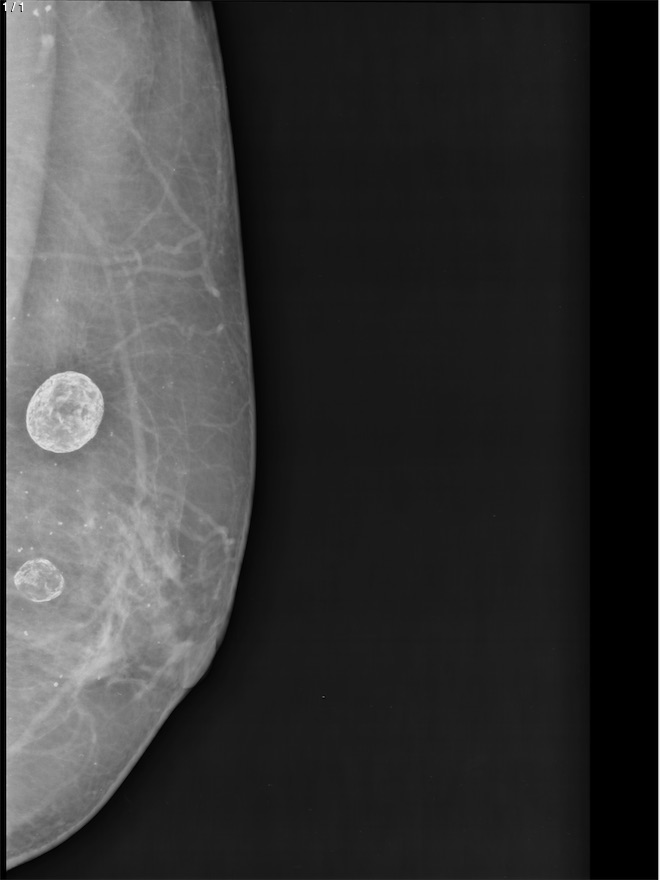

Bertha Ines Vazquez Salazar - Unnamed